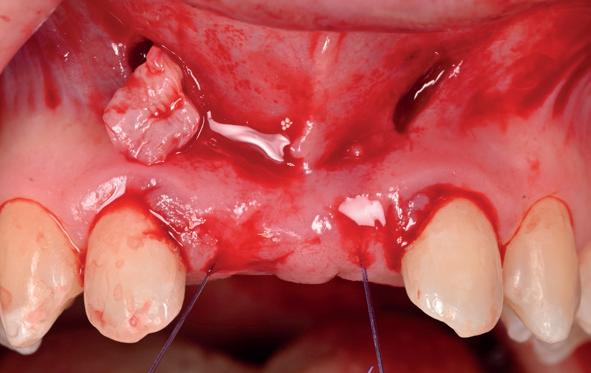

Voor de aanvulling zachte weefsels chirurgie werd gekozen voor de VISTA techniek, hierbij worden er twee incisies partial thickness flap hoog in de mucosa gemaakt, waarna er ruimte vanuit de incisies wordt getunneld tussen de gingiva en het periost door middel van VISTA tunnel instrumenten. Uit het palatum links werd een vrij gingivatransplantaat geoogst van 15x10 mm met een dikte van 3 mm, die voor inhechten werd geëpithelialiseerd. Als het epitheel niet wordt verwijderd, kan deze graft door

de mucosa heen groeien, dat ten koste gaat van de esthetiek. In het donorgebied wordt een collageen spons ingehecht, waardoor de patiënt daar minder last van heeft. Het bindweefsel wordt door de hul-

pincisies met hechtingen naar het buccale en coronale deel getrokken en aldaar ingehecht. Met twee incisies werd ook de emergence profile gecreëerd (afbeelding 6-13). Voor een goede genezing van het

5. Beginsituatie voor behandeling

6. VISTA techniek twee hulp incisies

7. Vervaardiging tunnel met tunnelinstrumenten

8. Geoogst bindweefseltransplantaat uit palatum

9. Na de-epithelialiseren van transplantaat

10. Inhechten van een collageenspons in het donorgebied

11. Middels hechtingen het op de juiste plek trekken van het transplantaat

12. Transplantaat ingehecht

13. Occlusaal beeld verdikking van de zachte weefsels